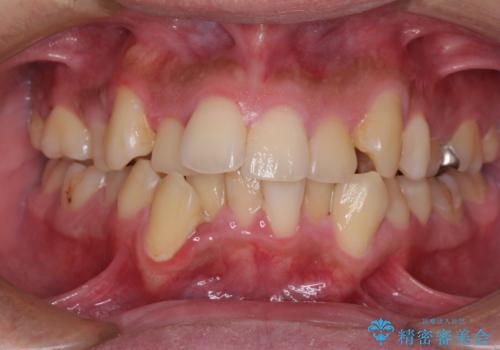

- 八重歯を気にして来院された患者様です。

上下左右の犬歯が八重歯になっており、口元にもやや突出感があるため、上下左右の小臼歯4本を抜歯し、ワイヤー装置にて矯正治療を行うこととしました。